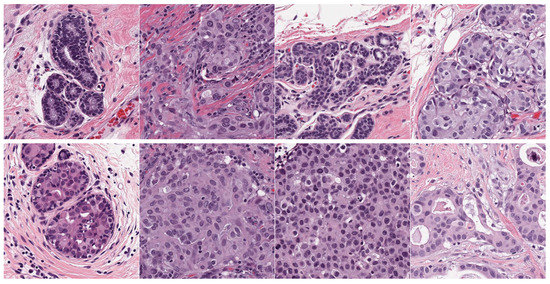

- Target dataset of breast cancer: the ICIAR-2018 (BACH 2018) Grand Challenge provided this dataset [58]. The images were uncompressed and in high-resolution mode (2040 × 1536 pixels). They consisted of H&E-stained breast histology microscopy images and were labeled as normal tissue, benign lesion, in situ carcinoma, or invasive carcinoma (see Figure 6). The labeling stage was achieved by two medical steps, utilizing identical acquisition cases, with an enlargement of 200. A total of 400 images were used (100 samples in each class). These images were chosen so that the pathology recognition could be independently distinguished from the visible organization and the tissue structure. The dataset was divided into 300 images for the training set and 100 for the testing set. The original image was divided into 12 nonoverlapping patches of 512 × 512 pixels in size.